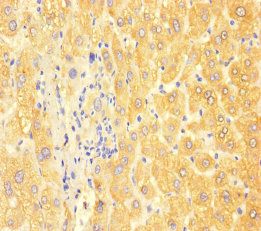

Immunohistochemistry of paraffin-embedded human liver cancer using CSB-PA12197A0Rb at dilution of 1:100